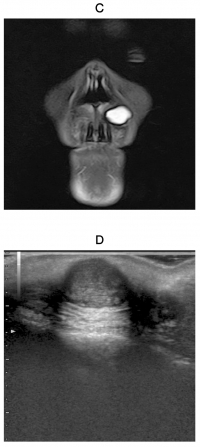

70歳の男性。鼻下部の無痛性の腫脹を主訴として来院した。10年以上前から自覚しており、緩徐に増大してきたという。初診時のMRI T1強調像と脂肪抑制T2強調像及び超音波検査の画像を示す。

考えられるのはどれか。1つ選べ。